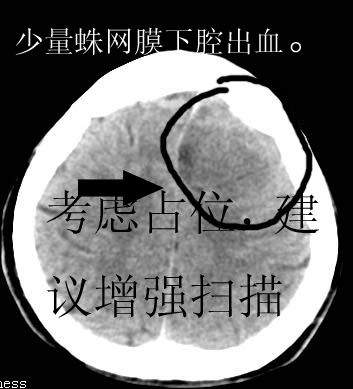

以下是引用卜一在2007-8-29 6:48:00的发言:[br]左侧额叶不均匀密度影,占位效应明显,界限不清。支持:占位性病变,建议增强!

以下是引用clj20在2007-8-29 9:47:00的发言:[br]蛛网膜下腔出血,左侧额叶不均匀密度影,占位效应明显,界限不清。支持:占位性病变,建议增强!

以下是引用xulianj在2007-8-29 20:15:00的发言:[br]蛛网膜下腔出血,左侧额叶不均匀密度影,占位效应明显,界限不清。支持:占位性病变,建议增强!

以下是引用jiangjing在2007-8-29 14:33:00的发言:[br]左侧额叶不均匀密度影[低密度为主,边缘见等密度环环绕]占位效应明显,界限不清。支持:占位性病变,建议增强! [br][br]